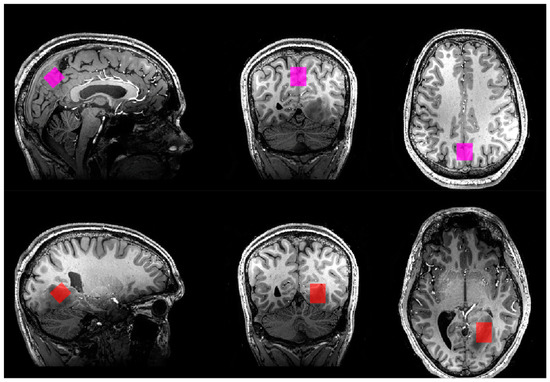

2.4. 1H-MRS

Semi-localization by adiabatic-selective refocusing (sLASER) sequences were used in the study [28]. A sLASER sequence for measuring the concentrations of glutamate, glutamine, creatine, phosphocreatine, total choline (tCho), N-acetylaspartate (NAA), N-acetylaspartyl glutamate (NAAG), GABA, lactate, and myo-inositol was acquired using the following sequence parameters: voxel size = 18.1 mm × 20.0 mm × 20.0 mm; TR = 4000 ms; TE = 32 ms; flip angle = 90 degrees; 32 transients; scan duration = 2 min. 8 s; 2048 complex data points; bandwidth = 4000 Hz. For patients, the voxels were placed in tumour regions (Figure 1). For both patients and control participants, a voxel of the same size as the tumour voxel was placed in the central praecuneus, covering both hemispheres in the parietal lobe (Figure 1).

Figure 1.

Voxel placement in all three planes in patient no. 1. (Top): praecuneus. (Bottom): tumour.